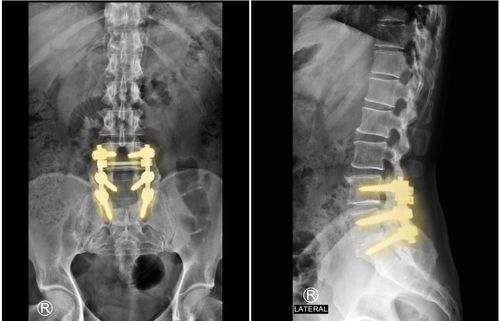

ALIF

TLIF

Posterolateral Fusion